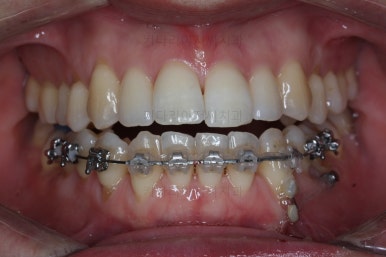

부산비수술교정 키다리아저씨치과에서 시행한 이번 치료의 결과입니다.

옆모습이 주걱턱 느낌이 많이 없어졌고 볼록하던 아랫입술도 뒤로 들어갔어요. 앞니가 거꾸로 물리지 않게 되어 웃거나 말하는 모습도 자연스러워졌어요.

아랫니 갯수가 모자라고 중앙이 맞지 않았고 짝이 안맞는 상황이었으나 비교적 잘 마무리를 했어요.

거꾸로 물리는 상황이 개선되었기 때문에 앞니나 어금니의 교합은 이전과 비교할 수 없을만큼 좋아졌지요.